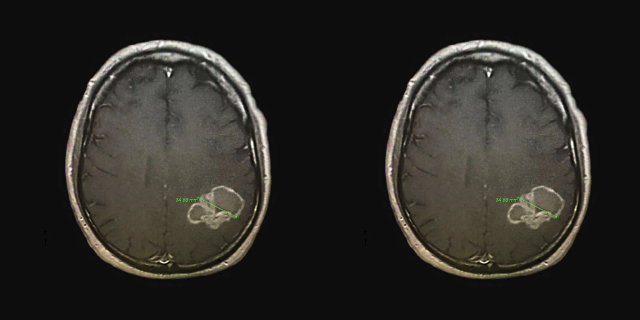

Carpenter 的脑肿瘤图像

CT 扫描发现 Carpenter 的右肺有一个肿块:肺癌已经转移到他的大脑。虽然他从不吸烟。